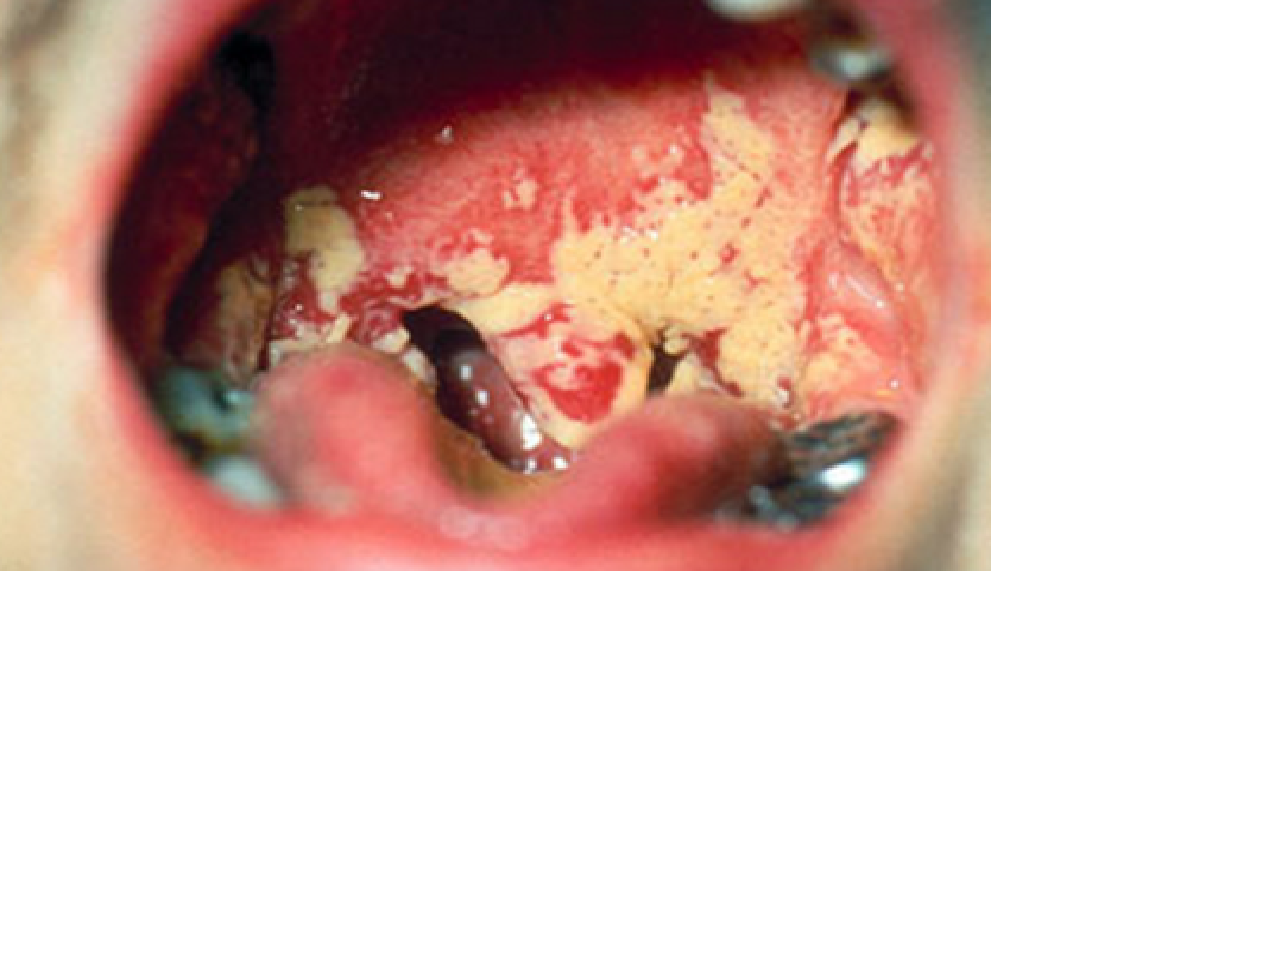

Candidiasis

1. Infección causada por levaduras del genero Candida

1. Mucosa oral

1. candidiasis mucocutanea crónica